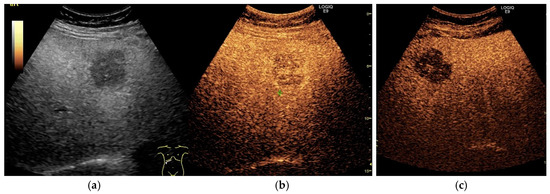

2.2. NAFLD-Related HCC: Could Conventional and Doppler US Differentiate between Focal Liver Lesions (FLLs)?

3. Contrast-Enhanced Ultrasonography (CEUS): An Add-on to the Diagnostic Power of Ultrasonography in NAFLD-Related HCC

3.2. Assessment of Fatty Liver Progression Using CEUS

3.3. The Evaluation of FLLs, Including HCC, in NAFLD Patients Using CEUS

3.3.1. Diagnostic Features of Hepatocellular Carcinoma on CEUS

3.3.2. HCC Particularities in NAFLD Patients